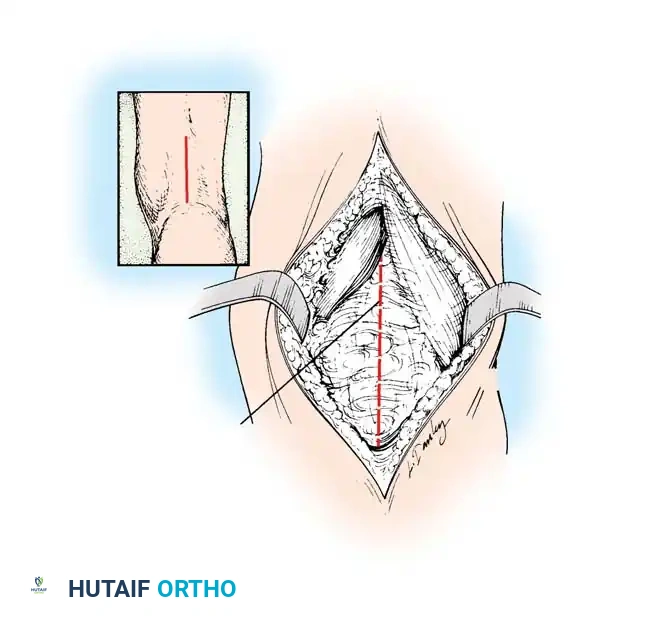

* Make medial and lateral posterior longitudinal incisions starting from the popliteal crease and extending 7 to 10 cm proximally. Alternatively, a single midline posterior incision can be utilized.

Incision mapping for posterior hamstring approach.

Medial Hamstring Lengthening:

* Divide the subcutaneous tissue and deep fascia strictly in line with the skin incision.

* Crucial Step: Identify and protect the posterior femoral cutaneous nerve in the proximal portion of the wound.

* Identify the hamstrings via blunt dissection. Isolate the semimembranosus muscle and incise its tendon sheath longitudinally.

* Divide the tendinous fibers of the semimembranosus on its deep (anterior) surface transversely at two distinct levels, leaving the underlying muscle fibers completely intact.